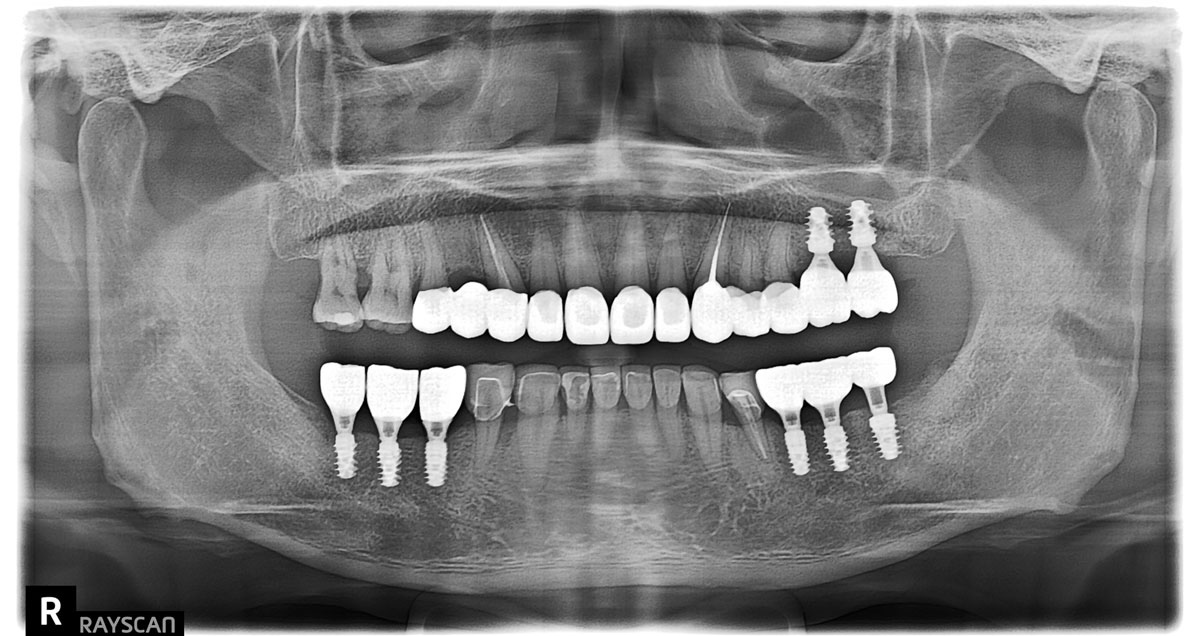

令謝先生印象深刻的是,蒔美牙醫的檢查很仔細,完全比照大型醫院的高階設備,清楚掌握病患缺多少骨頭、骨質好不好。在醫生的衛教下,他了解到精準評估骨頭狀況,未來植牙才會真正穩固耐用。

與國際並行,引進頂尖植牙設備

讓謝先生驚訝的是,和傳統牙醫不同,他植牙全程是在無菌正壓手術室進行,在診所就能擁有大醫院的醫療品質。

手術全程透過先進的「X-Guide 藍光植牙導航系統」輔助,這種尖端技術如同外科的達文西手臂,讓牙肉牙骨下的狀況一覽無遺,避免人為出錯。

比起傳統植牙精準11倍,高安全,傷口小、恢復快。

謝先生長年戴活動假牙,又有牙周病,植體的選擇更顯重要。採用來自瑞士頂尖大廠的士卓曼植體,其材質堅硬強度高,可有效減少補骨。

植體周圍發炎可說是當今植牙一大殺手,士卓曼植體採頂級精密工藝,專利活性親水表面處理,讓細菌不易滲透,抑制發炎危機。